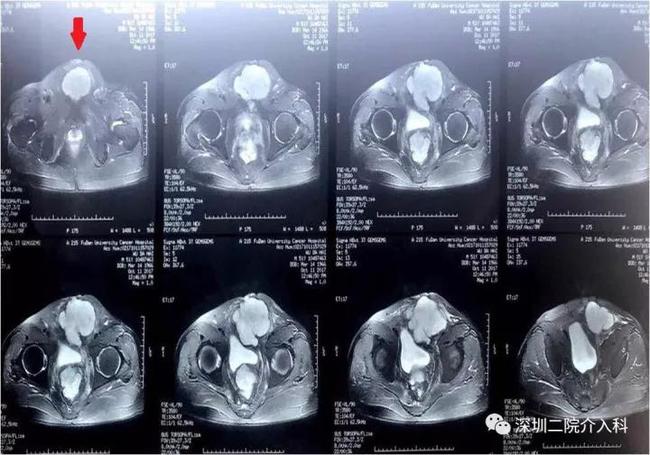

图为MRI显示腹壁上一高信号占位(也就是红色箭头所指发白的球体):